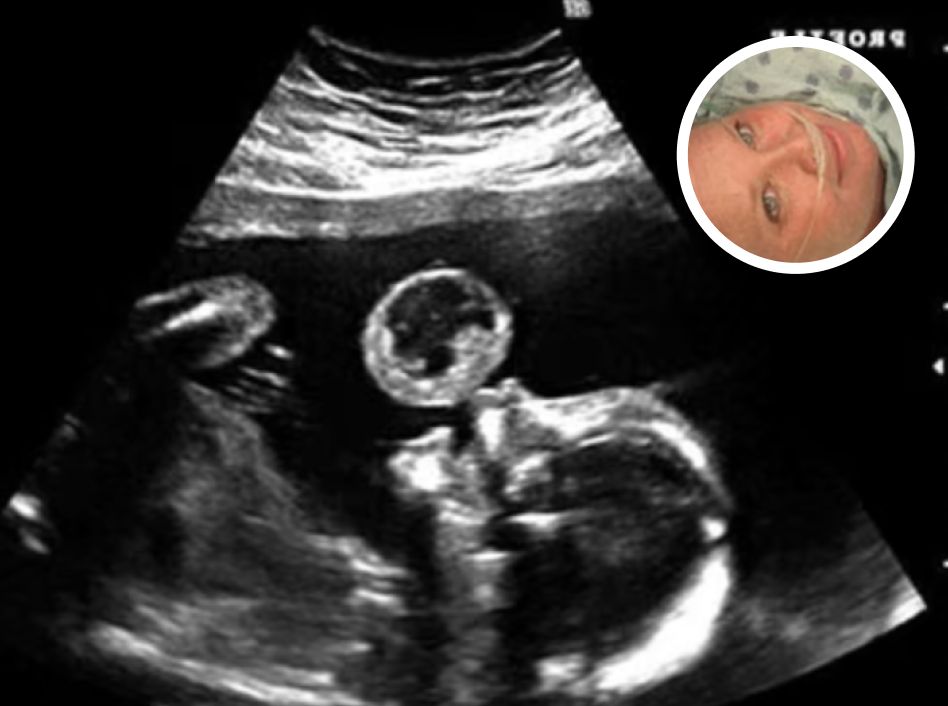

Mom Thinks Her Baby Is Blowing Bubble In Ultrasound, Then Doctors Discover What It Really Is Posted on: December 31, 2025December 31, 2025